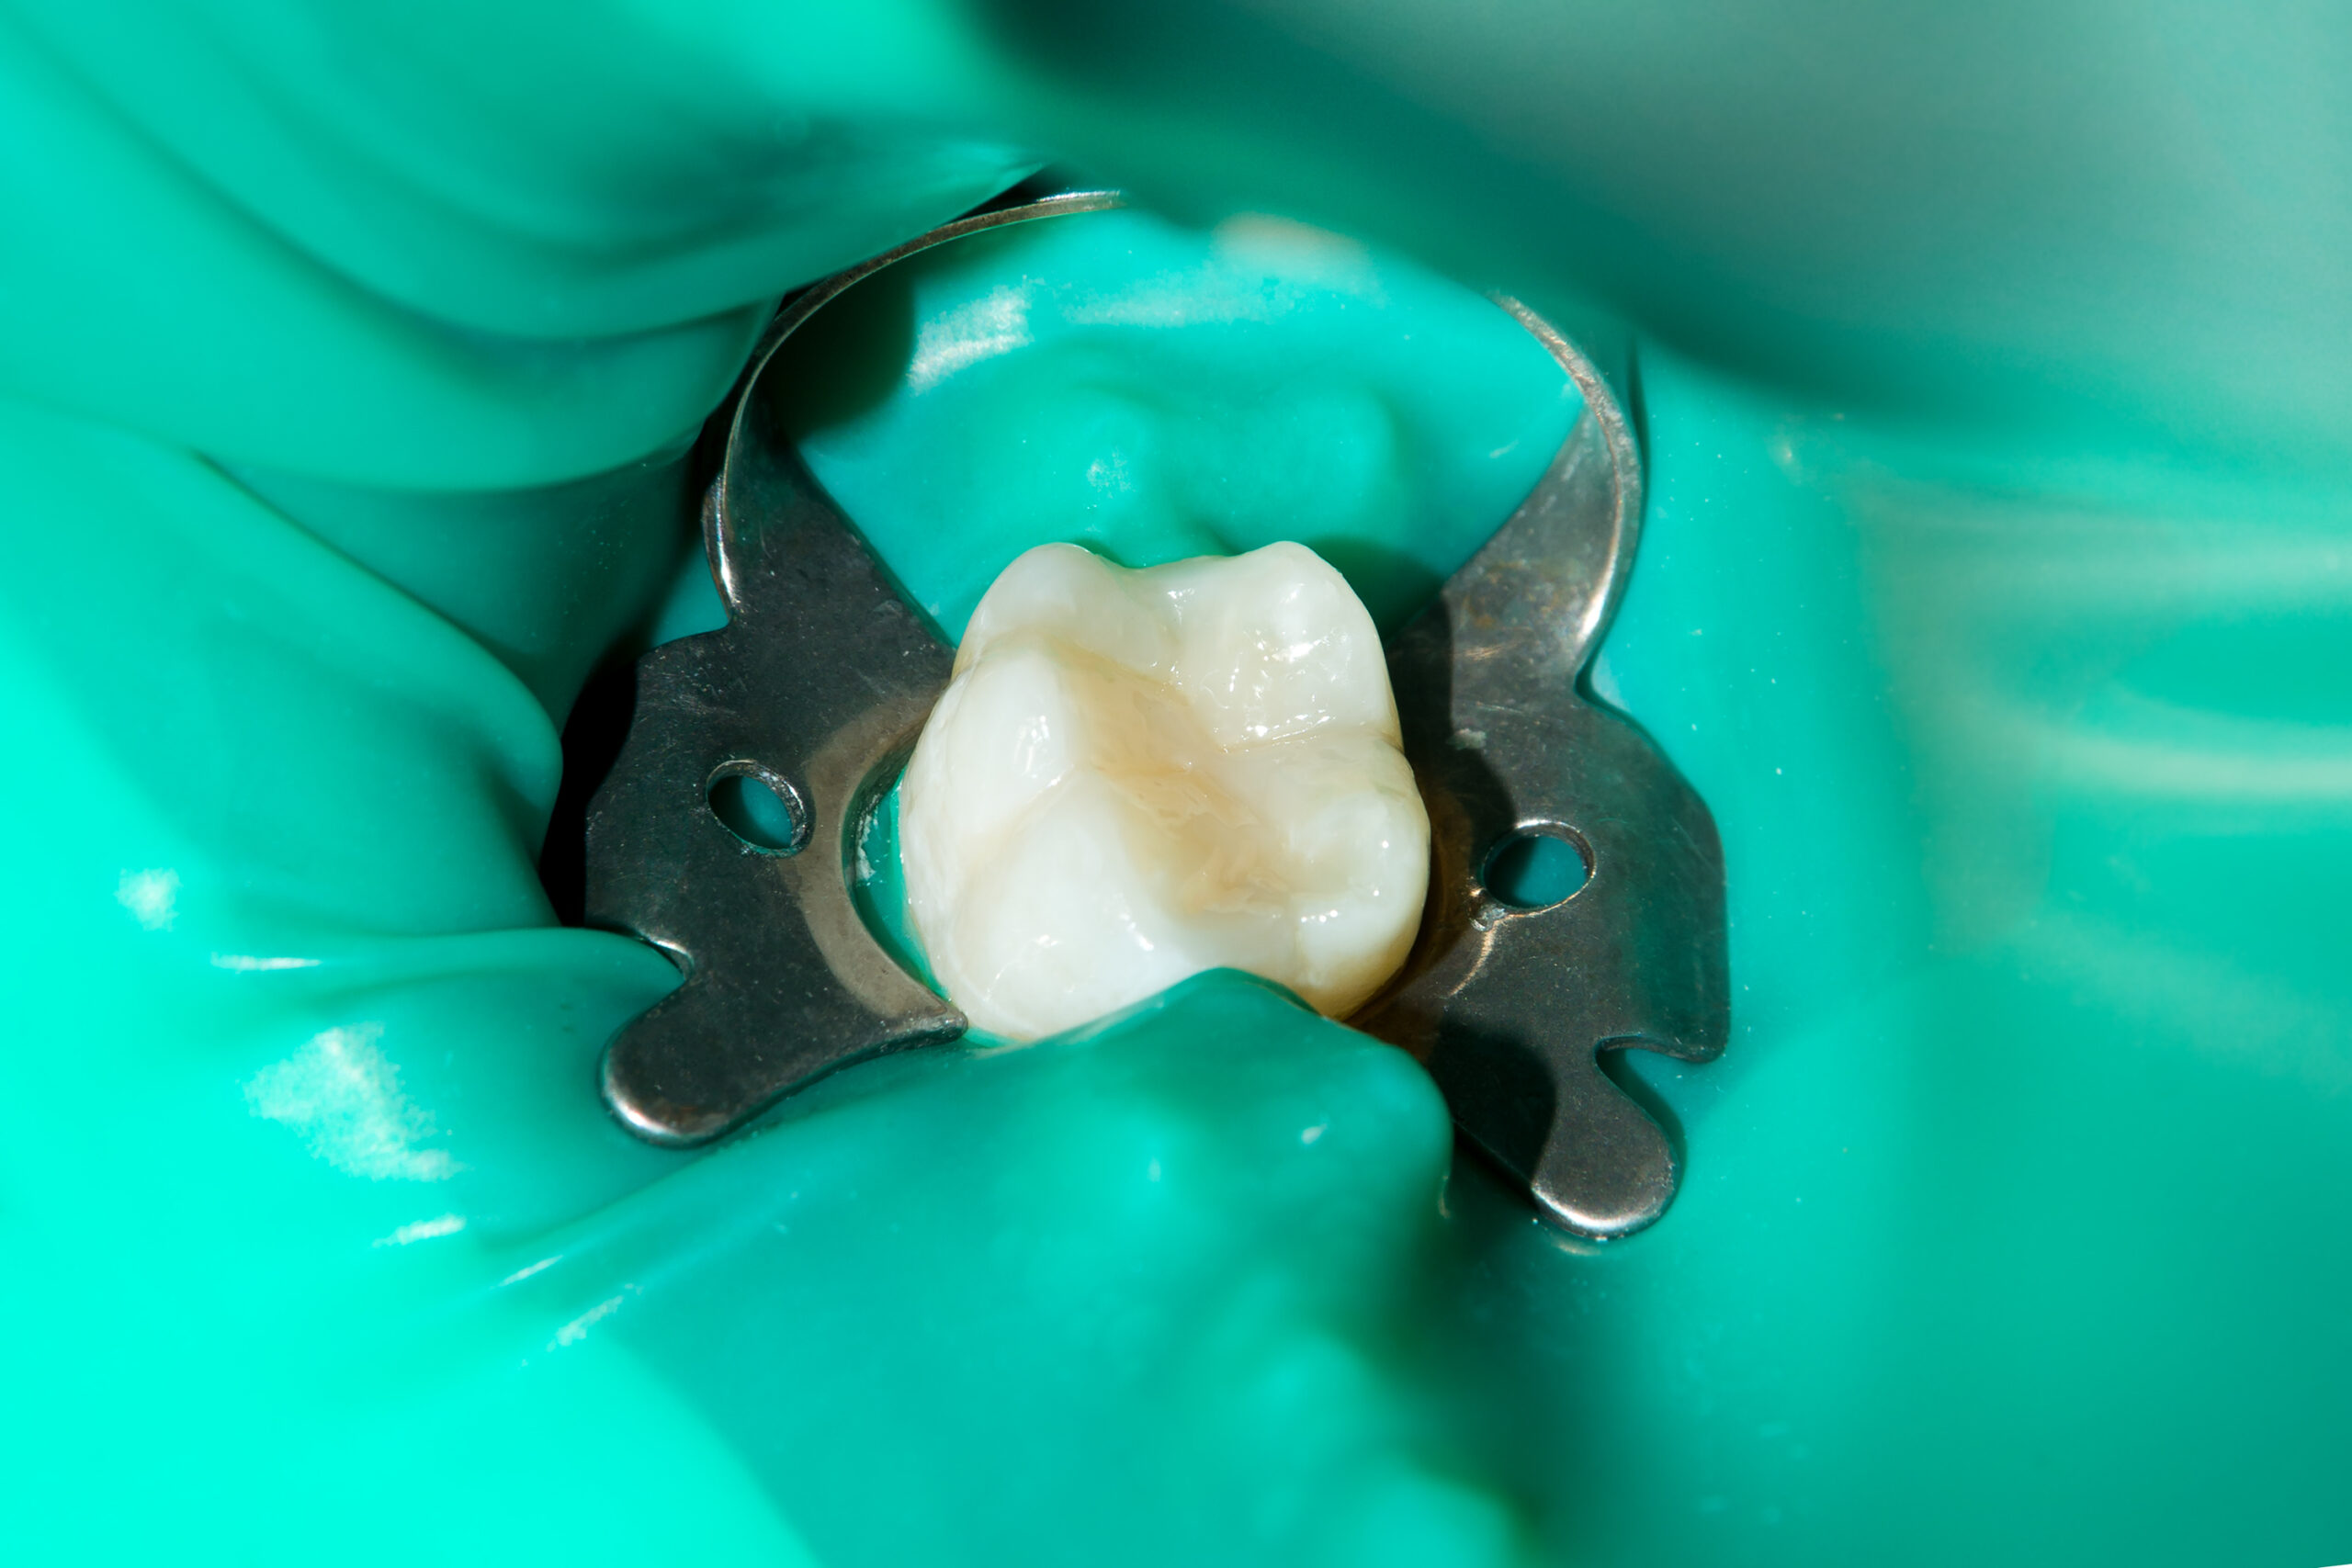

ラバーダムを用いた根管治療

ラバーダムを使用することで、感染防止・治療精度の向上・薬剤からの粘膜保護・安全性の向上など多くのメリットがあります。当院ではほぼすべてのケースで使用しています。

治療前

治療後

| 主訴 | 左下奥歯が痛い、歯ぐきの腫れ。 前医で抜歯を提案されたがセカンドオピニオン希望でご来院。 |

|---|---|

| 治療期間 | 約半年(6か月) |

| 治療費 | 約5万円 |

| 治療内容 | 前医ではラバーダム不使用であったため、ラバーダム、マイクロスコープ下にて根管治療を施術。 痛みは消失したが腫れは治らなかったため、意図的再植を行い腫れは消失した。治療後のレントゲンは意図的再植後3年経過したもの。 |

| 治療のリスク | マイクロスコープやCTを使用し、可能な限り精密な根管治療を行っていますが、歯根の形態や病変の大きさ、過去の治療履歴などにより、治癒が得られない場合があります。 また、治療後に再感染や歯根破折が生じることもあり、その場合は再治療や抜歯が必要となることがあります。 治療結果には個人差があり、すべての症例で同様の経過を保証するものではありません。 |